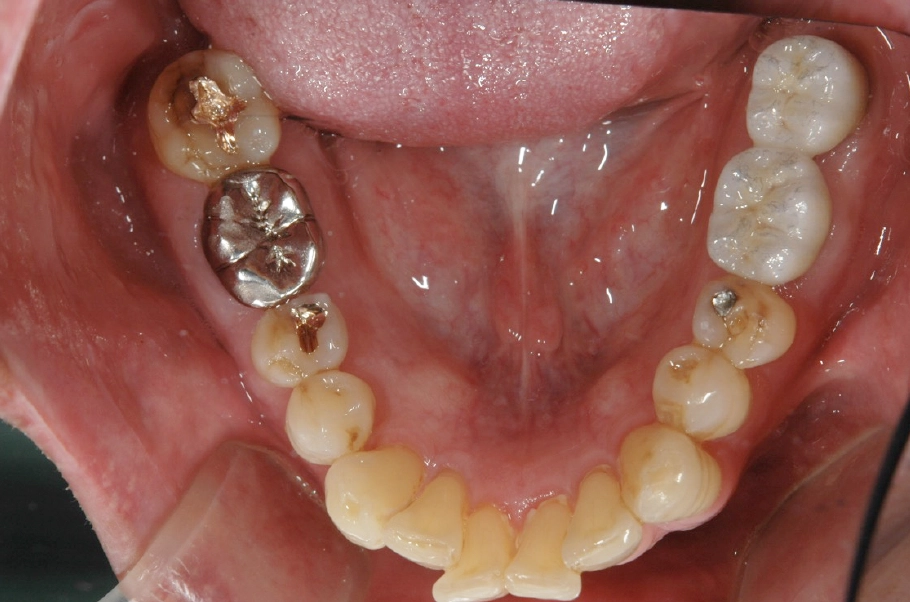

| 主訴 | 親知らずのせいで⻭をなくしてしまった |

|---|---|

| 診断名 | ⻭の⽋損 |

| 年齢・性別 | 50歳・男性 |

| 治療期間・回数 | 4ヶ⽉・4回 |

| 治療方法 | インプラント |

| 費用 | 799,700円 |

| 治療上のリスク |

|